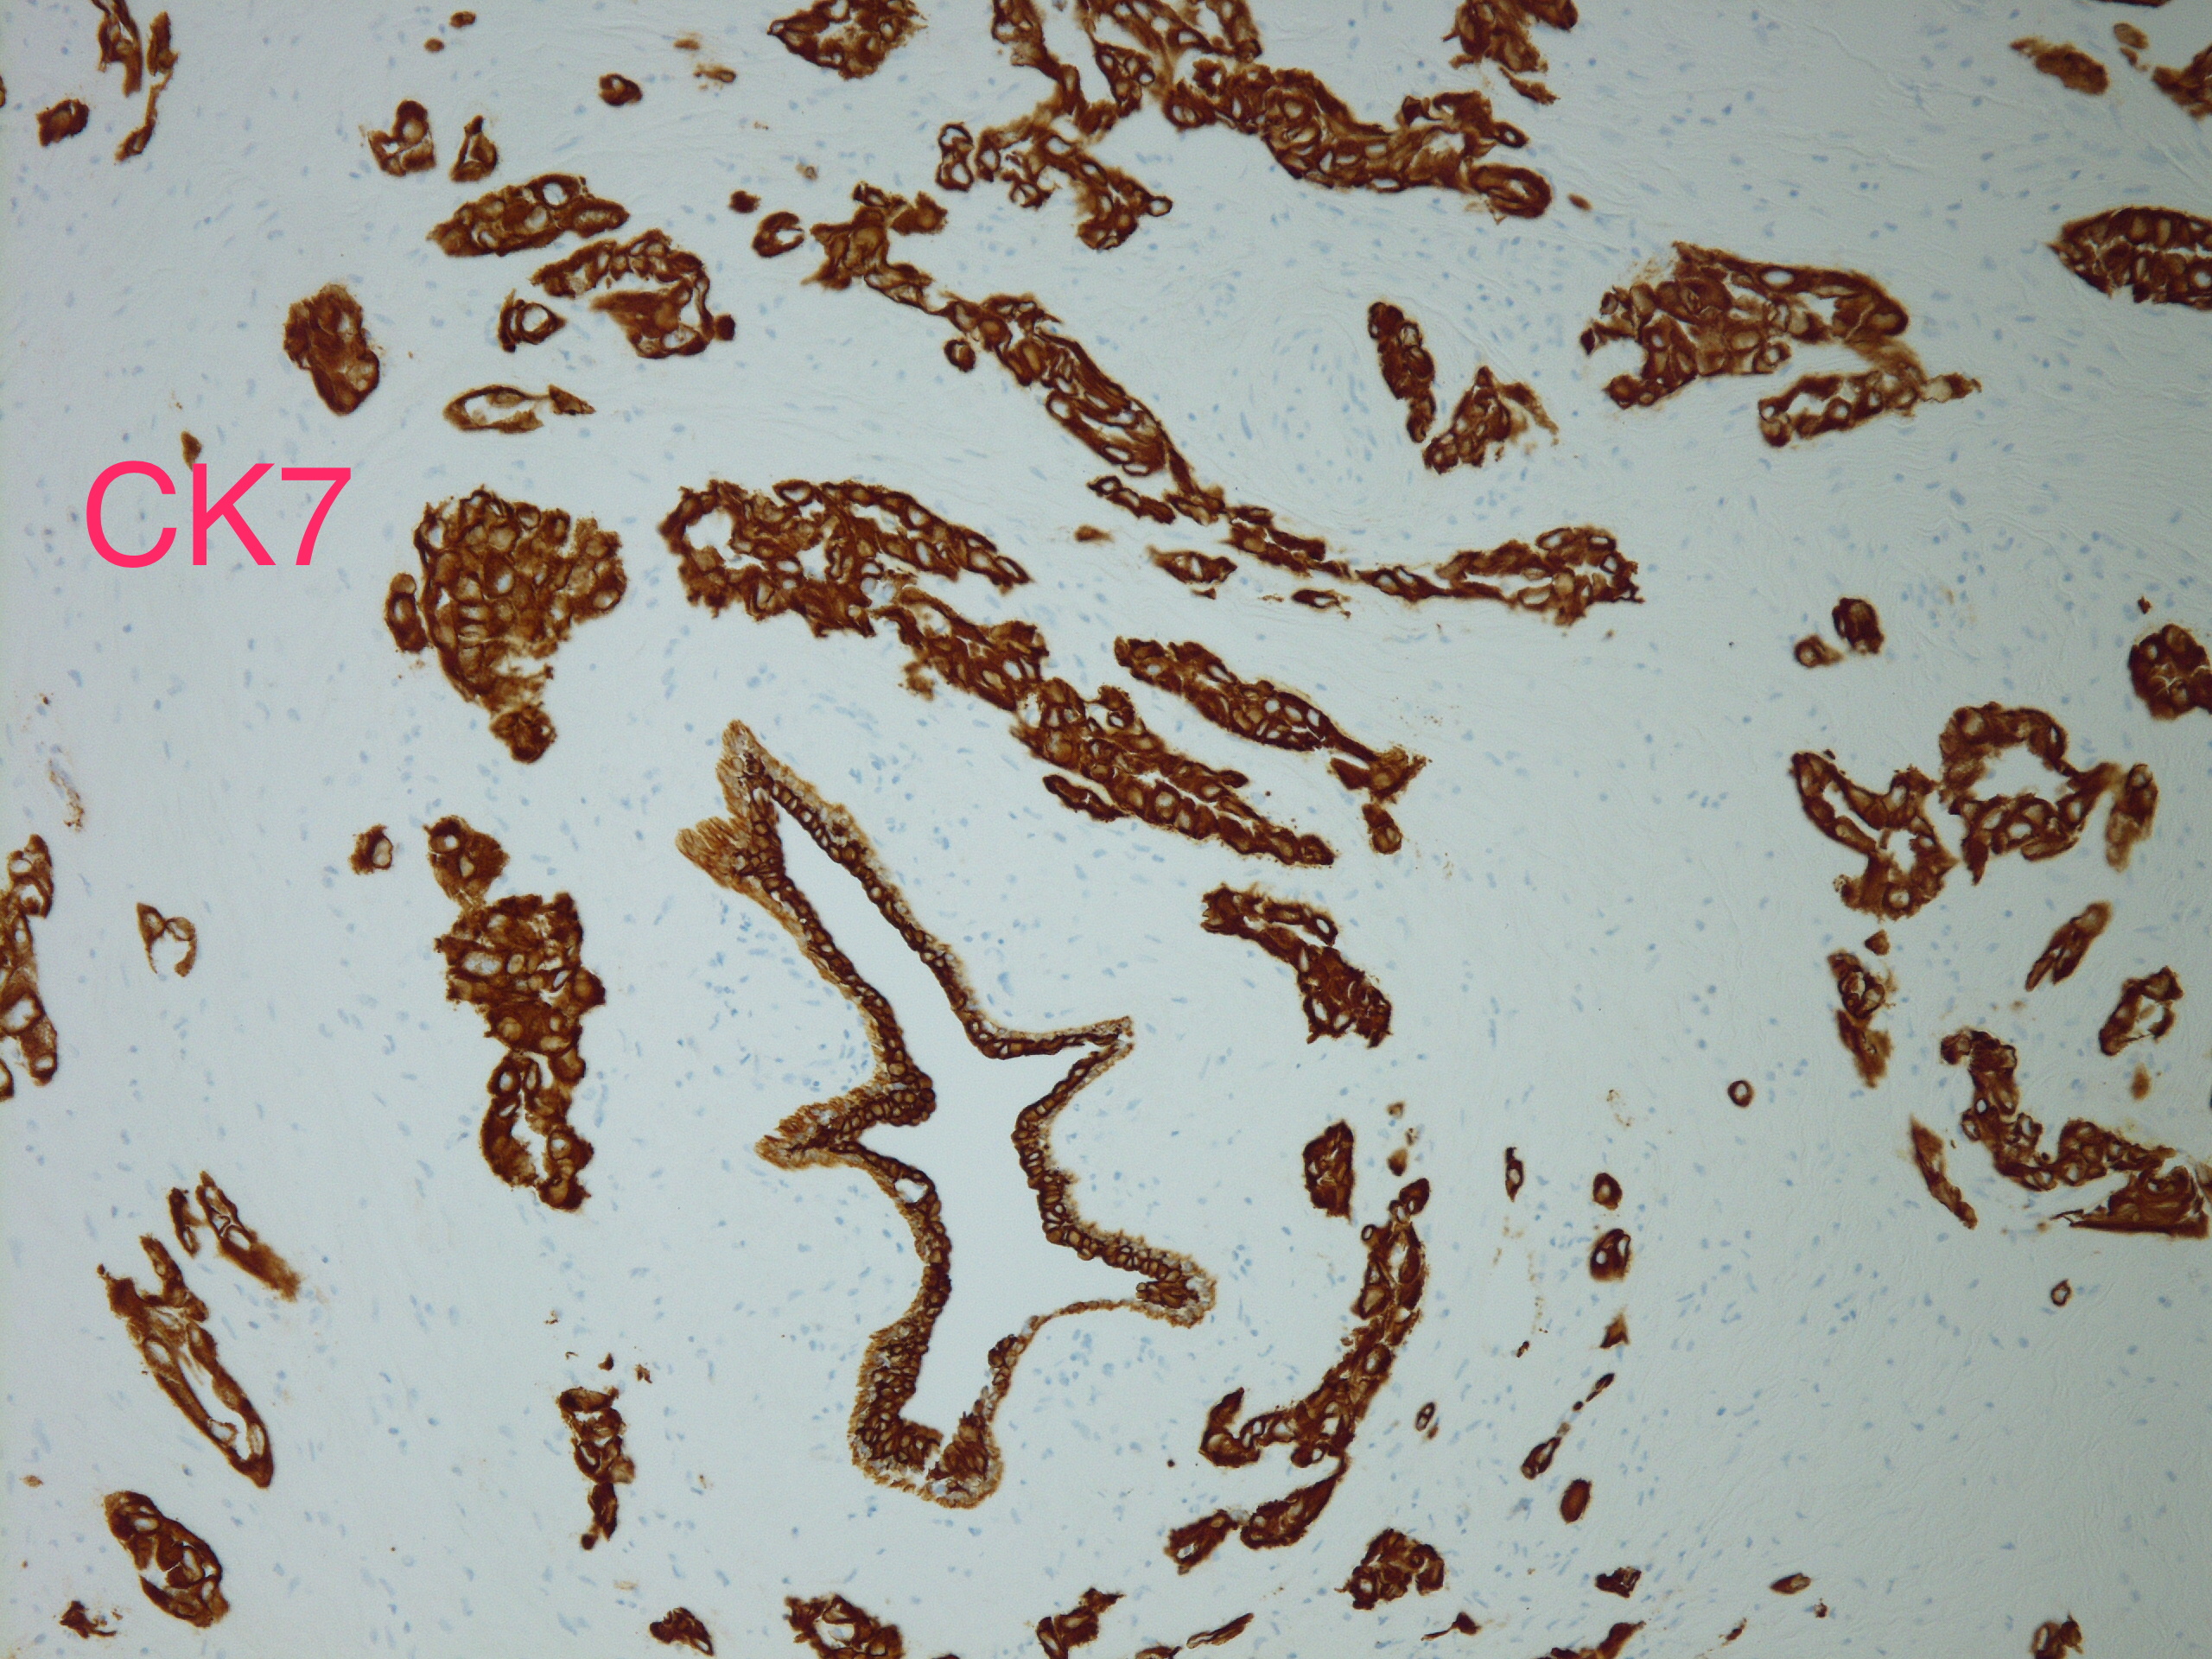

分享赵老师的一个病例:女,70岁,发现左侧乳腺肿块,2.5cm,行穿刺活检。无其他病史。

INVASIVE ADENOCARCINOMA, NUCLEAR GRADE 3.COMMENT:Multiple immunostains were ordered to determine it is a primary or metastatic tumor.

AddendumImmunostains were performed on the block. The tumor cells are positive for CK7, TTF-1, focally and weakly positive for ER, negative for PR and GATA-3, GCDFP, mammaglobin. The immunostain results support this is a metastatic carcinoma from pulmonary primary. This patient reportedly has metastatic adenocarcinoma of lung origin.AddendumNapsin A is positive, supporting a lung primary.

此例最后考虑是来自肺的转移性腺癌

约1/3的乳腺转移癌以乳腺肿块为首发症状,因为病人多采用全身或姑息治疗,所以穿刺诊断可以避免不必要的手术治疗。存在导管原位癌提示乳腺原发,钙化也多见于乳腺原发肿瘤(除卵巢浆液性癌)@杨鹏 淄博市妇幼保健院 群管 @车拴龙 吉林 :对于形态较特别的乳腺癌也是要提高警惕的